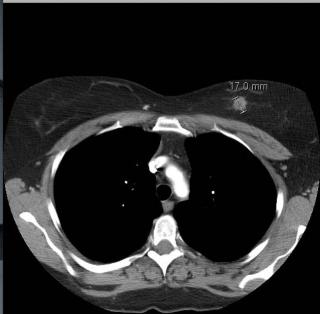

Для проведения исследования пациентке необходимо горизонтально расположиться на подвижной части томографа. С помощью специального катетера внутривенно вводят контраст. Кушетку перемещают под сканирующее кольцо и запускают аппарат. Лучи проходят сквозь молочную железу, датчики улавливают скорость прохождения их через ткани и проектируют на экране компьютера послойные изображения обследуемой области. С помощью компьютерной обработки снимки накладываются друг на друга, и в итоге создается трехмерная модель грудной клетки.

Расшифровкой томограмм занимается рентгенолог. Он детально рассматривает изображения и делает подробное описание обнаруженных патологий. Заключение по результатам компьютерной томографии и КТ снимки используется лечащим врачом при постановке окончательного диагноза и определения дальнейшей методики лечения.

До 90% случаев болезней молочных желез возможно выявить с помощью УЗИ либо маммографии. Компьютерная томография (КТ) молочной железы нужна в качестве дополнительного метода исследования, без которого иногда невозможно поставить верный диагноз. Для проведения компьютерной томографии применяется томограф. Метод основан на действии рентгеновского луча, который пронизывает ткани органа и выполняет сканирование. Результат КТ отображается на рентгеновской пленке в виде ряда поперечных срезов.

КТ молочных желез позволяет оценить, насколько опухоль операбельна, есть ли ее врастание в грудную клетку. Также КТ дает возможность сделать выводы о радикальности операции, отсутствии гематом и абсцессов в области лечения. Метастазы опухоли груди могут распространяться также и на другие органы, поэтому КТ необходима для принятия верного решения о том, насколько возможным и целесообразным является проведение операции.

Во время проведения томографии кушетка с лежащей на ней пациенткой медленно заходит в кольцо томографа. Длительность процедуры КТ обычно составляет не больше 30 минут. В течение процедуры пациентке нужно лежать, не двигаясь, это необходимо для получения наиболее достоверных результатов обследования. Рентгенологический излучатель томографа направляет лучи под разными углами, эти лучи имеют разную интенсивность. Все сигналы подаются на компьютер и на нем анализируются. Итоги диагностики в виде двухмерных срезов молочных желез выводятся на экран. Медперсонал при проведении процедуры находится в смежном кабинете.

КТ с контрастом выполняется в случаях, когда нужно очень четко разделять нормальные и аномальные структуры в человеческом организме. Такая дифференцировка достигается посредством усиления сигнала от больных тканей. Эффект контрастирования при КТ основывается на том, что большинство опухолей, особенно, злокачественных, кровоснабжается лучше, чем здоровые ткани. Поэтому контрастное вещество будет накапливаться в них, давая картину отличия от прочих тканей. Кроме того, контраст необходим для изучения состояния сосудов – вен, артерий. На снимках КТ контраст будет выделяться белым цветом, что позволит хорошо изучить этот участок.